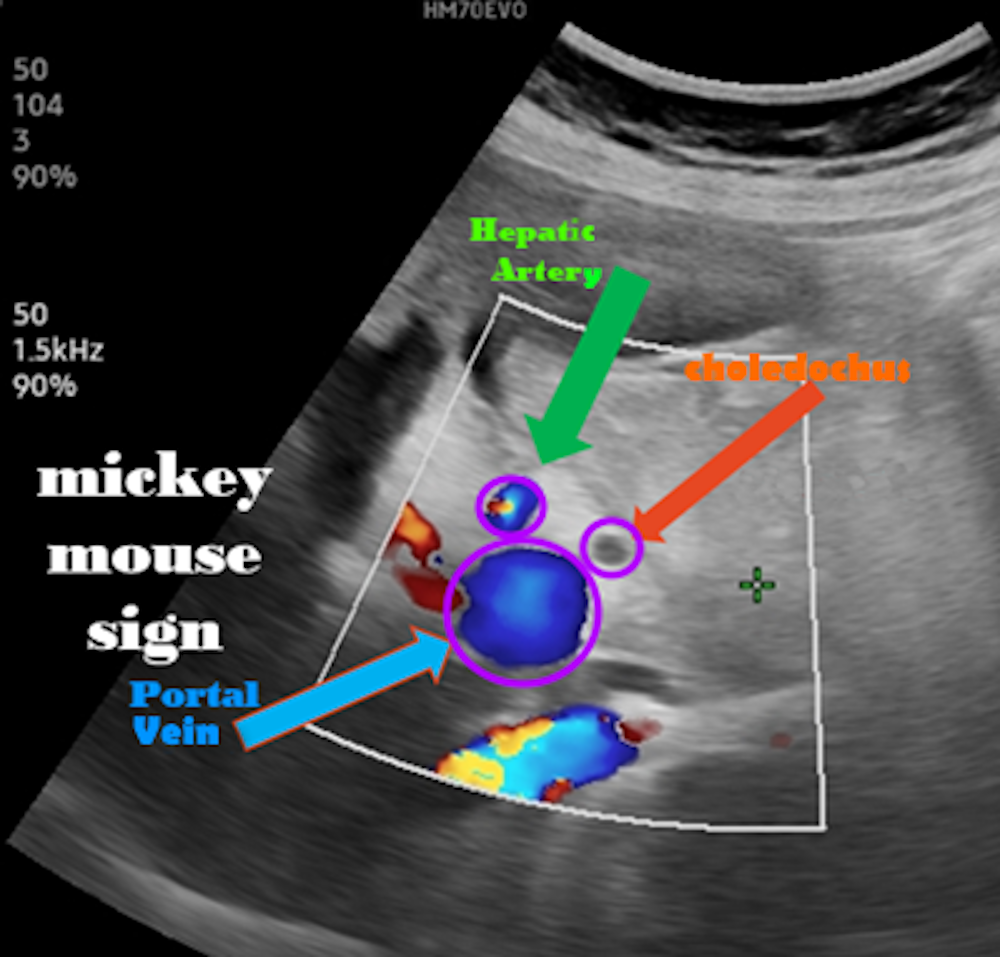

A normal gallbladder measures approximately 10 cm in length and 2–4 cm in diameter, with a wall thickness of less than 3 mm. Gallstones typically appear as hyperechoic foci that produce posterior acoustic shadowing (Figure 7). In acute cholecystitis, increased wall thickness, pericholecystic fluid, and a positive sonographic Murphy’s sign may be observed (Figures 7 and 8). In cases with biliary sludge, a homogeneous fine internal echogenicity is noted (Figure 8). Polyps appear attached to the gallbladder wall and do not move with changes in patient position (Figure 9). Visualization of the main portal triad during gallbladder ultrasonography is crucial for identifying hepatobiliary system pathologies (Figure 10).